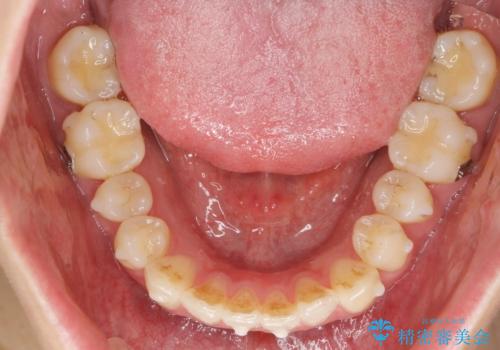

- 目立つ前歯のねじれを改善したい、と矯正治療を希望され来院されました。

マウスピース矯正インビザラインを用いて綿密に治療計画を練り、美しい歯並びを手に入れるべく治療計画を立案します。

左側の奥歯は後方移動を行うことで、理想的な噛み合わせに整えるとともに、前歯の突出感も同時に改善することができました。